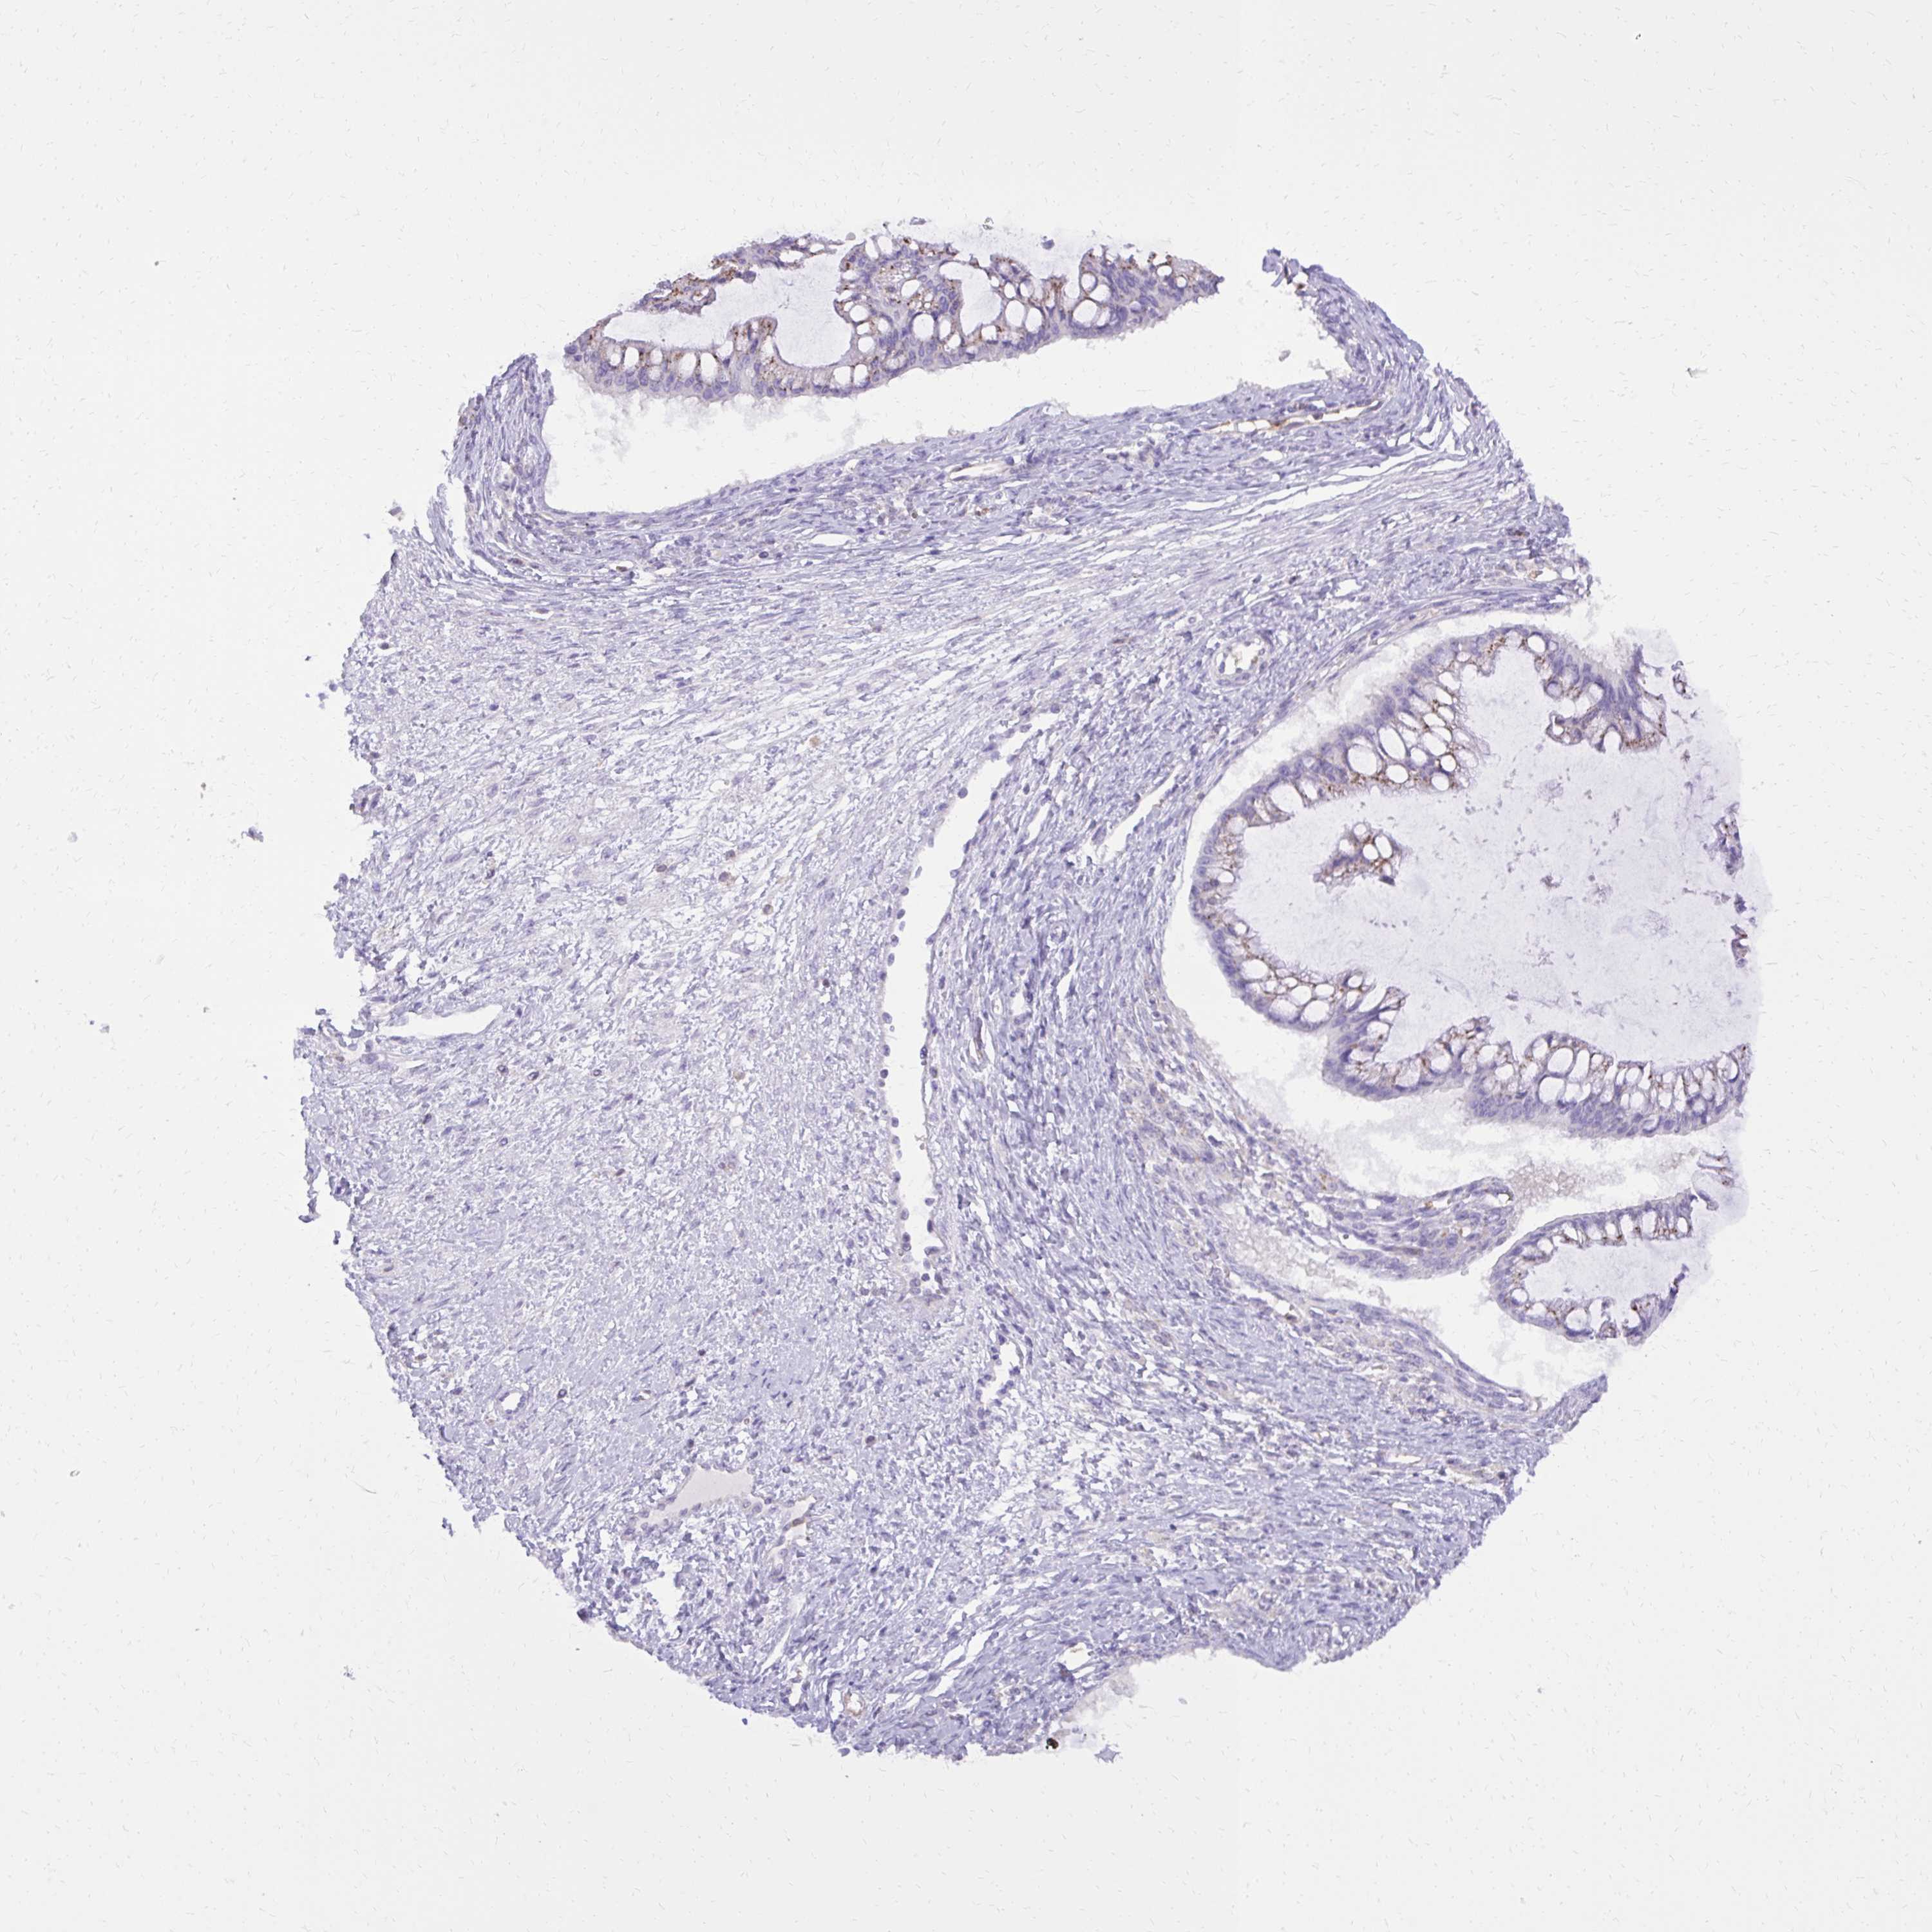

OVARIAN CANCER - Protein expressioni

A mouse-over function shows sample information and annotation data. Click on an image to view it in a full screen mode. Samples can be filtered based on level of antibody staining by selecting one or several of the following categories: high, medium, low and not detected. The assay and annotation is described here.

Note that samples used for immunohistochemistry by the Human Protein Atlas do not correspond to samples in the TCGA dataset.

Antibody stainingi

Antibody staining in the annotated cell types in the current human tissue is reported as not detected, low, medium, or high, based on conventional immunohistochemistry profiling in selected tissues. This score is based on the combination of the staining intensity and fraction of stained cells.

Each image is clickable and will lead to virtual microscopy that enables deeper exploration of all samples and also displays staining intensity scores, fraction scores and subcellular localization as well as patient and tissue information for each sample.

Antibody HPA051282

Antibody HPA055838

Antibody CAB001515

Cystadenocarcinoma, serous, NOS

Cystadenocarcinoma, mucinous, NOS

Carcinoma, endometroid